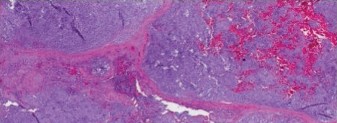

Figure 8–18 A

Figure 8–18 B

Discussion

The correct answer is (D). This is a chondrosarcoma. Figure 8–18A shows tumor surrounding all bony trabeculae, and the higher power view seen in Figure 8–18B demonstrates a very cellular tumor with pleiomorphism. Chondrosarcoma is treated

with wide resection and if applicable, reconstruction. Preoperative radiation and/or chemotherapy have no usefulness in treatment of chondrosarcoma. Postoperative x-ray is shown inFigure 8–